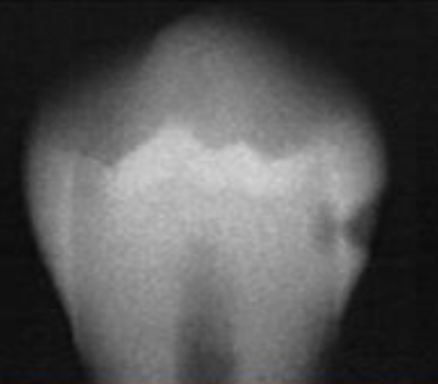

Q

Classify the caries

A

initial caries (IC)